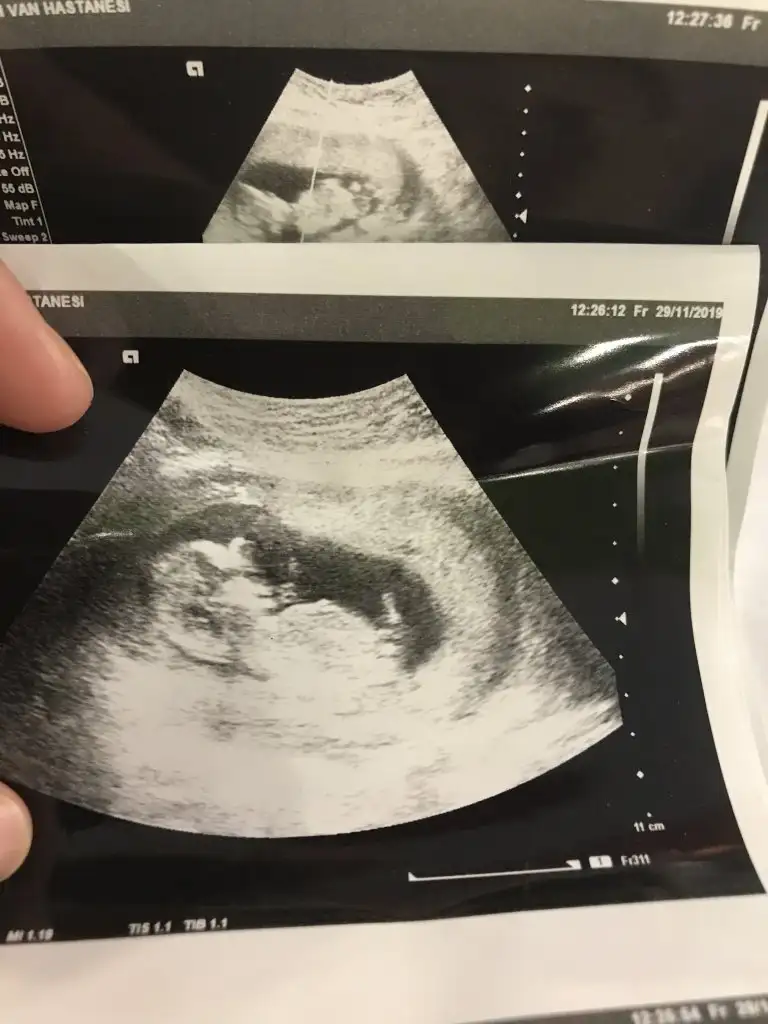

13. Haftalık 11 ve 12. Haftalıkken doktora gitmedik kontrolümüz 13. Haftaya denk geldi o yüzden bu başka da var ama net değil ki atayım ben yine deerkek gibi başka usg var kaç haftalık

erkek gibi başka usg var kaç haftalık